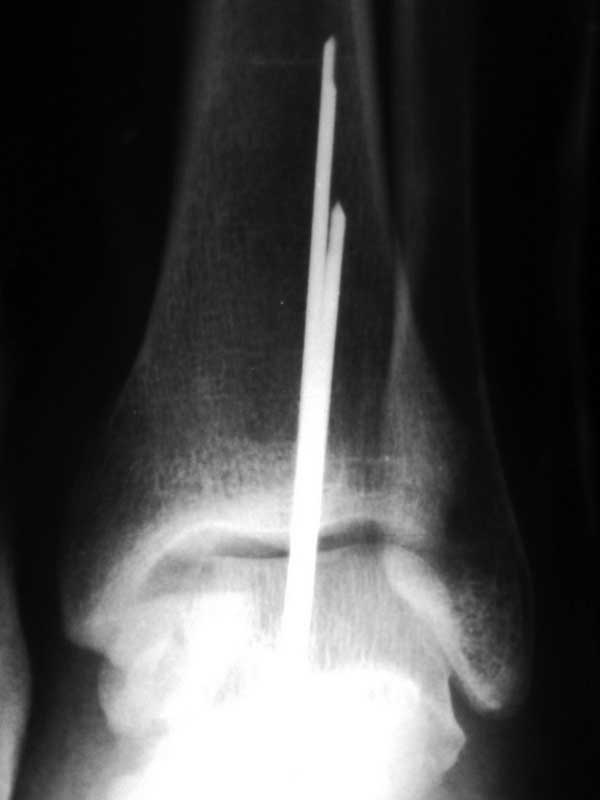

[Ortho] Переломовывих таранной кости

Да, видимо, это чрезкожная фиксация спицами... у меня тоже только"??????"

>> Прямая проекция